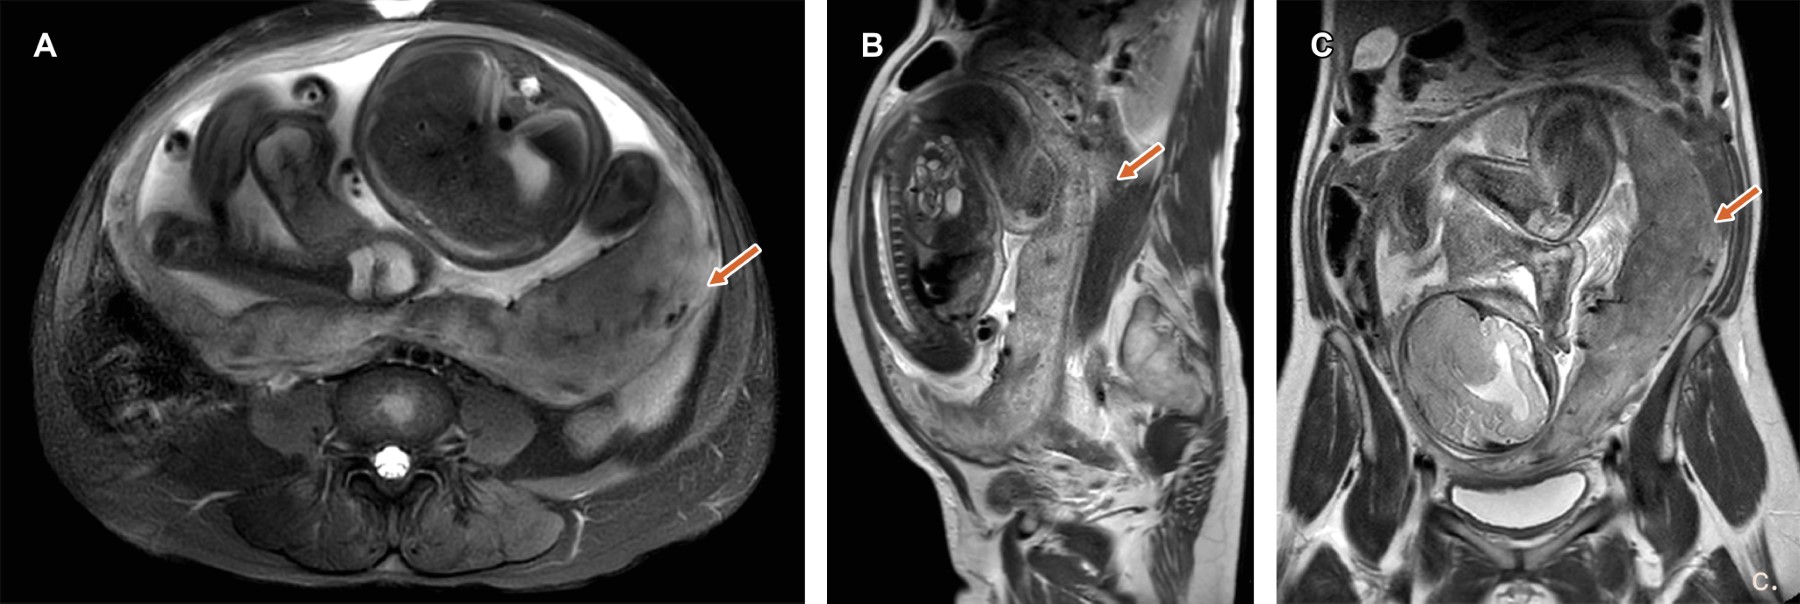

Las características por imagen en RM son: bandas oscuras interplanetarias en T2, pérdida de la línea retroplacentaria, vascularización anormal del lecho placentario, abultamiento uterino-placentario, adelgazamiento del miometrio, masa exofítica focal e interrupción de la pared de la vejiga (Tabla 1),1 dichos hallazgos se ejemplifican en las Figuras 1 y 2 en donde se identifica la placenta de bordes lobulados, heteroge?nea, con zonas lineales y otras puntiformes de baja sen?al en su interior. Coexisten zonas de pe?rdida de la interfase con el miometrio, así como localización de la placenta hacia el borde inferior del orificio del cervical interno.

Figura 1